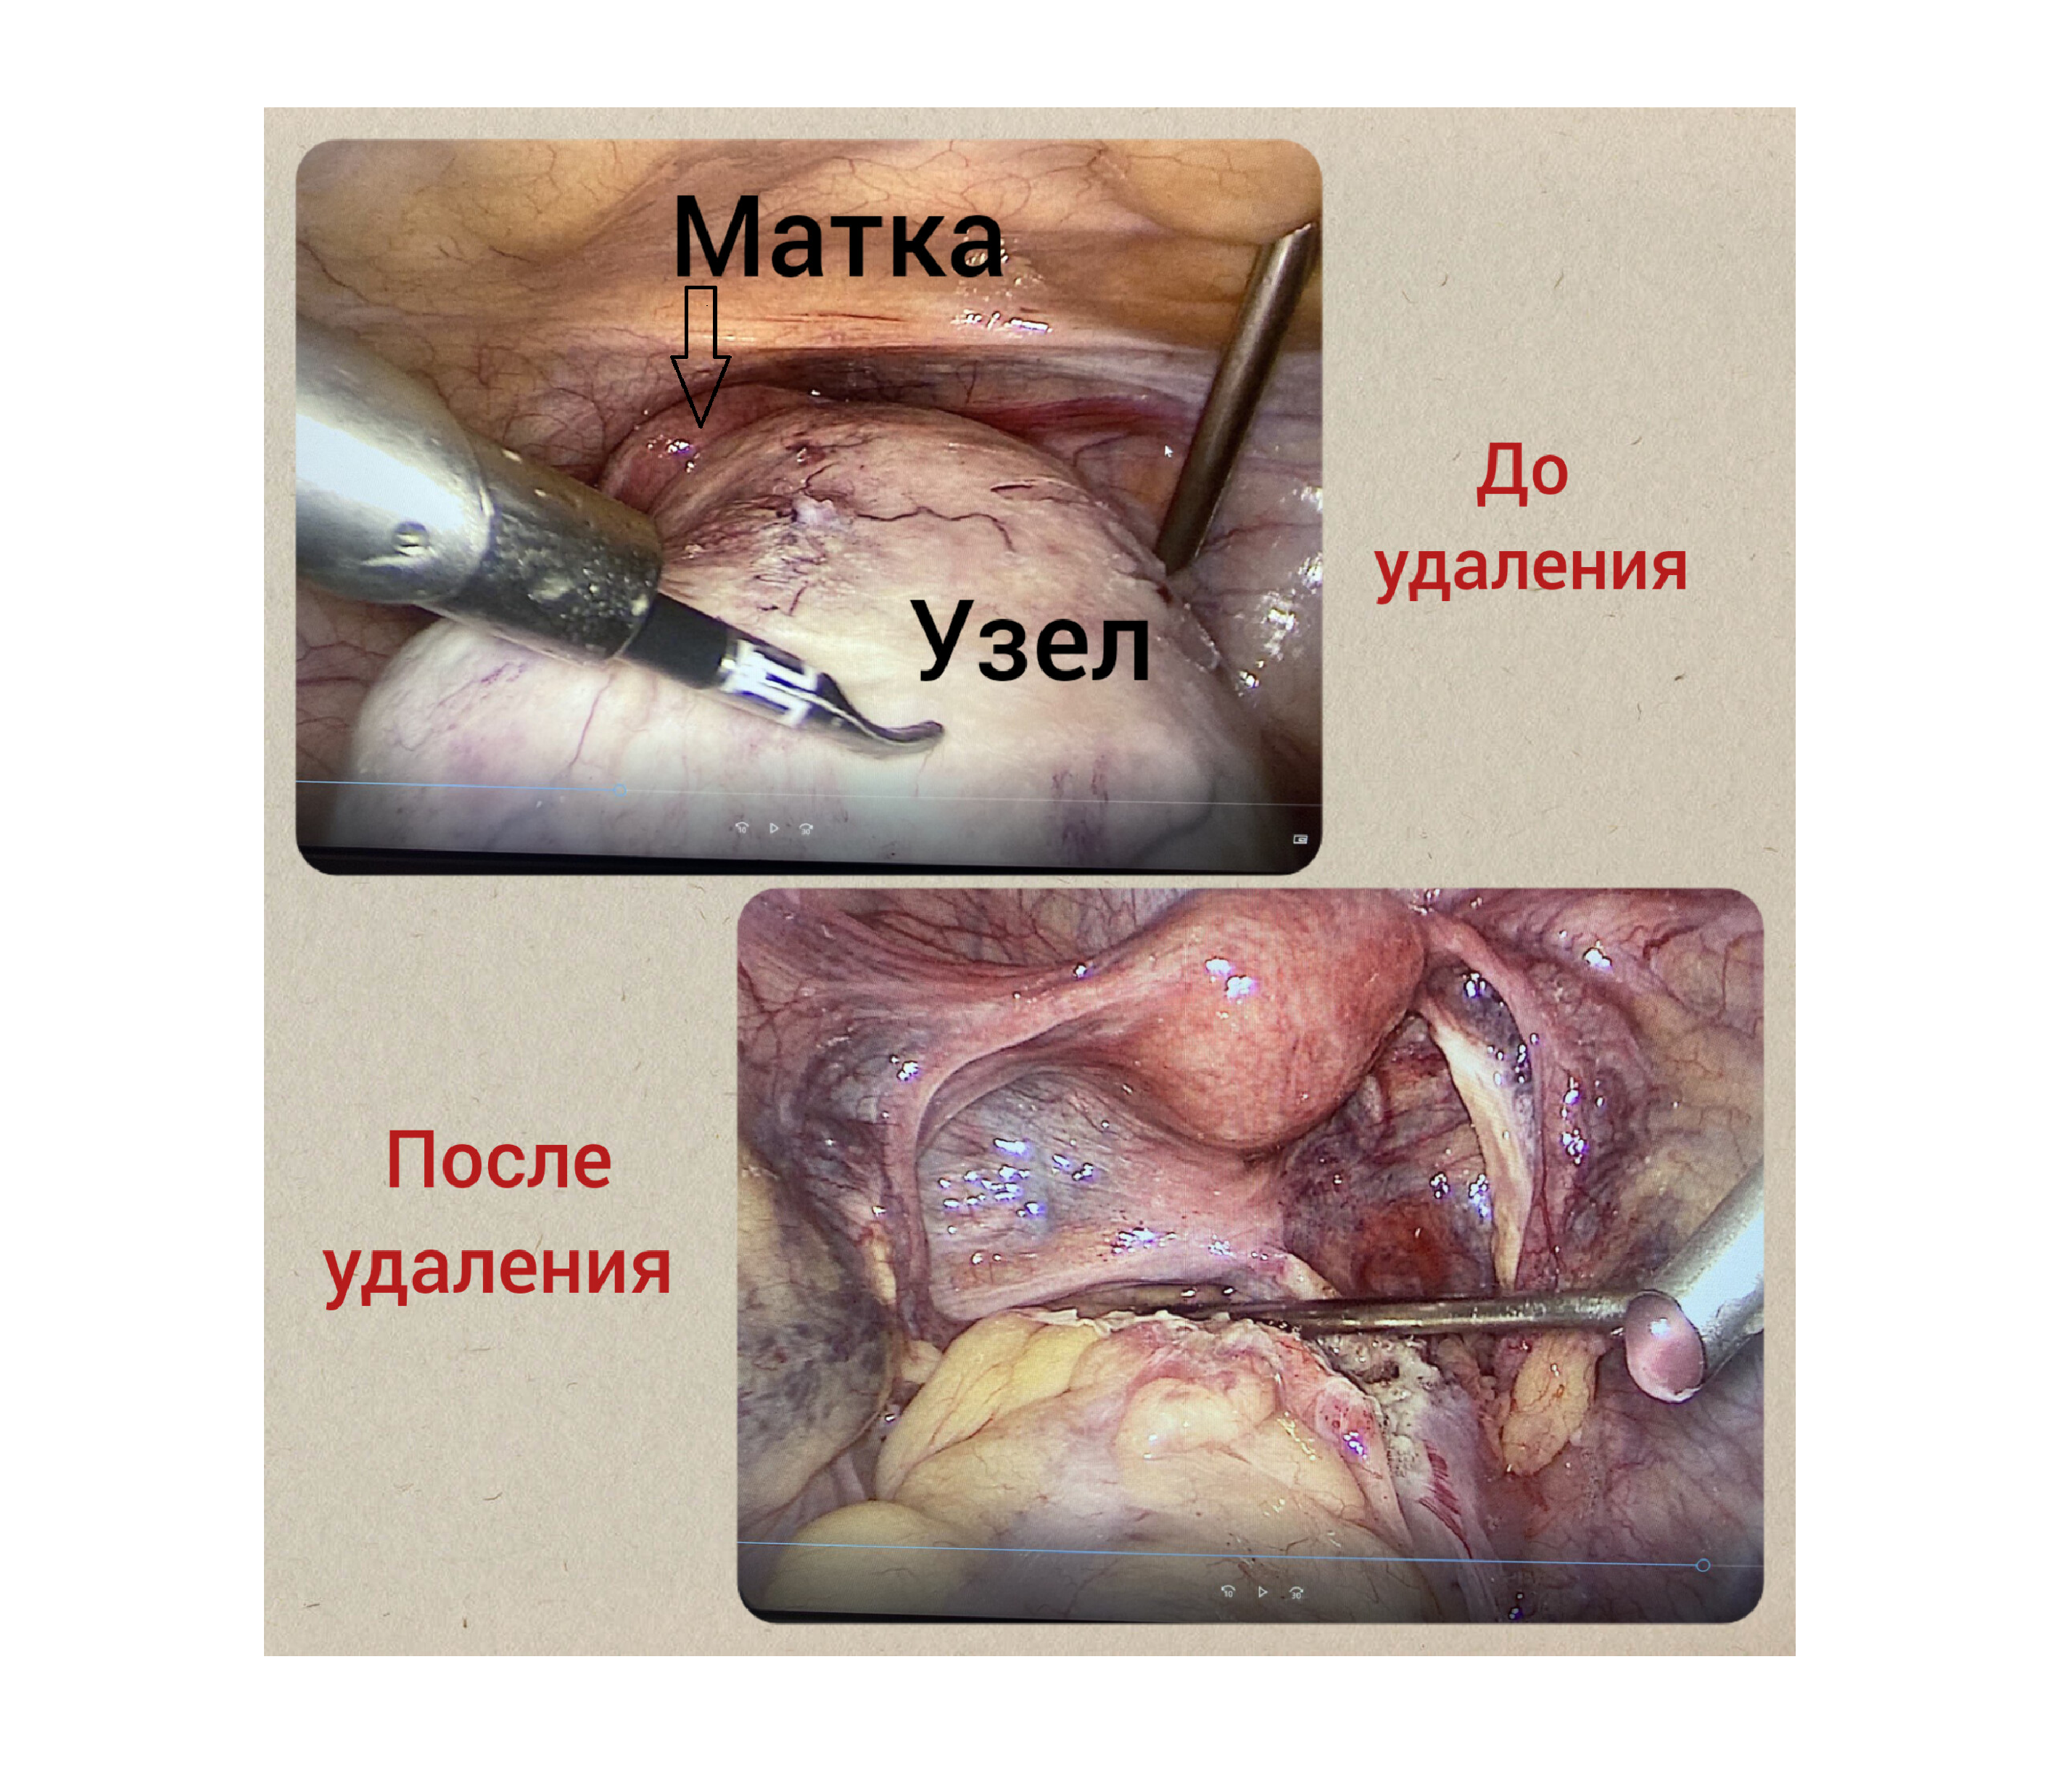

Сохранение репродуктивной функции при хирургическом лечении в КГБУЗ «КМКБ № 4».

Подробнее...

28.02.2023

Врачи КГБУЗ «КМКБ № 4» спасли женщину, удалив редкую разновидность миомы матки/

Подробнее...